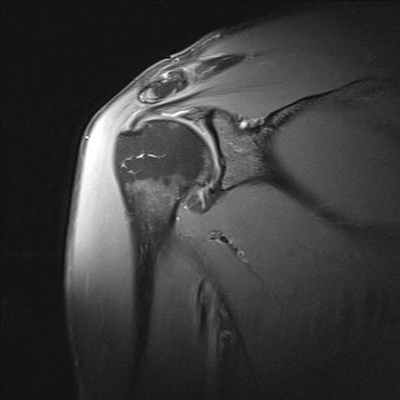

МРТ плечевого сустава

Плечелопаточный периартрит (периартроз, периартикулярные поражения области плечевого сустава) - собирательный термин всех периартикулярных поражений области плечевого сустава. Нередко боли в области плечевого сустава вызваны не поражением самого сустава, а околосуставных мягких тканей. Наиболее частой причиной острой или хронической боли в области плечевого сустава является дегенеративно-воспалительное поражение сухожилий мышц, участвующих в движениях плеча (тендиниты). От чрезмерной физической нагрузки (у маляров, спортсменов и людей других профессий) сухожильные волокна растягиваются и надрываются. В конечном итоге развивается воспалительный процесс. Острый период с резкими болевыми ощущениями у таких пациентов длится обычно несколько недель, и при эффективном лечении интенсивность болей в плече снижается, функция сустава восстанавливается. Однако благоприятное течение заболевания с полным выздоровлением заканчивается далеко не у всех. У многих больных при неблагоприятном развитии патологического процесса боли в плече не проходят, а подчас усиливаются не только при физической нагрузке, но и в покое, приобретают постоянный характер. Движения в суставе, как правило, сопровождаются хрустом различной интенсивности. В далеко зашедших случаях может возникнуть тугоподвижность сустава, атрофия мышц и остеопороз головки плечевой кости. При рентгеновском исследовании чаще всего определяется кальцификация (отложение солей) в суставных сумках и в окружающих сустав тканях. МРТ дает полную картину патологических изменений в периартикулярных тканях на ранних этапах заболевания - это отек в области сухожилий, их истончение или неполный разрыв, наличие выпота в суставных синовиальных сумках, атрофия отдельных групп мышц и др. Среди основных показаний к МРТ исследованию плечевого сустава являются нестабильности в суставе и разрывы вращательной манжеты плеча.

Нестабильность плечевого сустава отмечается при слабой фиксации головки плечевой кости в суставной впадине лопатки, которая приводит к повышенной подвижности в суставе и часто к развитию вывихов и подвывихов при травмах, определенных положениях руки (например, при бросании предметов из-за головы вперед). Если диагностика вывихов не представляет особых затруднений при обычном рентгенологическом исследовании, то подвывихи не всегда четко визуализируются при данном методе лучевой диагностики. МРТ диагностика в этих случаях позволяет визуализировать даже незначительные нарушения взаимоотношений головки плечевой кости и суставной впадины лопатки.

Разрывы вращательной манжеты плеча являются наиболее частой причиной болевого синдрома в плечевом суставе во всех возрастных группах взрослого населения и невозможности поднять или отвести руку. МРТ диагностика при данной травме позволяет визуализировать как полный разрыв связок, так и частичное их повреждение. Как правило, сопутствующими осложнениями повреждений вращательной манжеты плеча является скопление жидкости в субакромиальной и поддельтовидной сумках (находятся между мышцами), что также хорошо выявляется при МРТ исследовании. А восстановление разрыва сухожилий вращательной манжеты является сложной хирургической операцией.